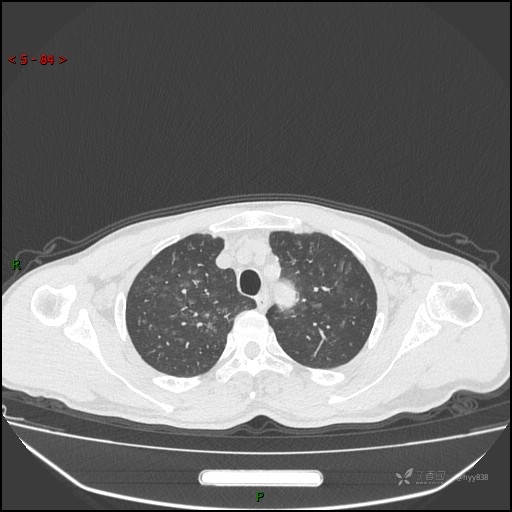

呼吸科电话会诊病例:过敏性肺炎 VS 吸烟相关间质性肺炎 VS 尘肺……结果公布~

性别:男

年龄:55岁

简要病史:渐进性呼吸困难。

胸部CT平扫

电焊工尘肺 (2)